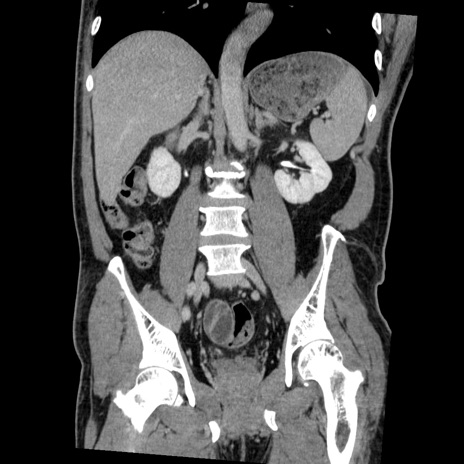

症例22(冠状断像)

【症例】50歳代男性

【主訴】腹痛

【現病歴】AVMからの被殻出血のため回復期リハ病棟入院中。 本日午後3時頃急に下腹部痛が出現した。

【既往歴】AVM、被殻出血、虫垂炎、高血圧

【身体所見】意識晴明、左半身不全麻痺、会話の理解は良好、36.5°C、腹部:膨隆、全体に板状硬、下腹部正中に圧痛点あり、反跳痛-、筋性防御不明、右下腹部にope scar

【データ】WBC 9400、CRP 0.06

横断像